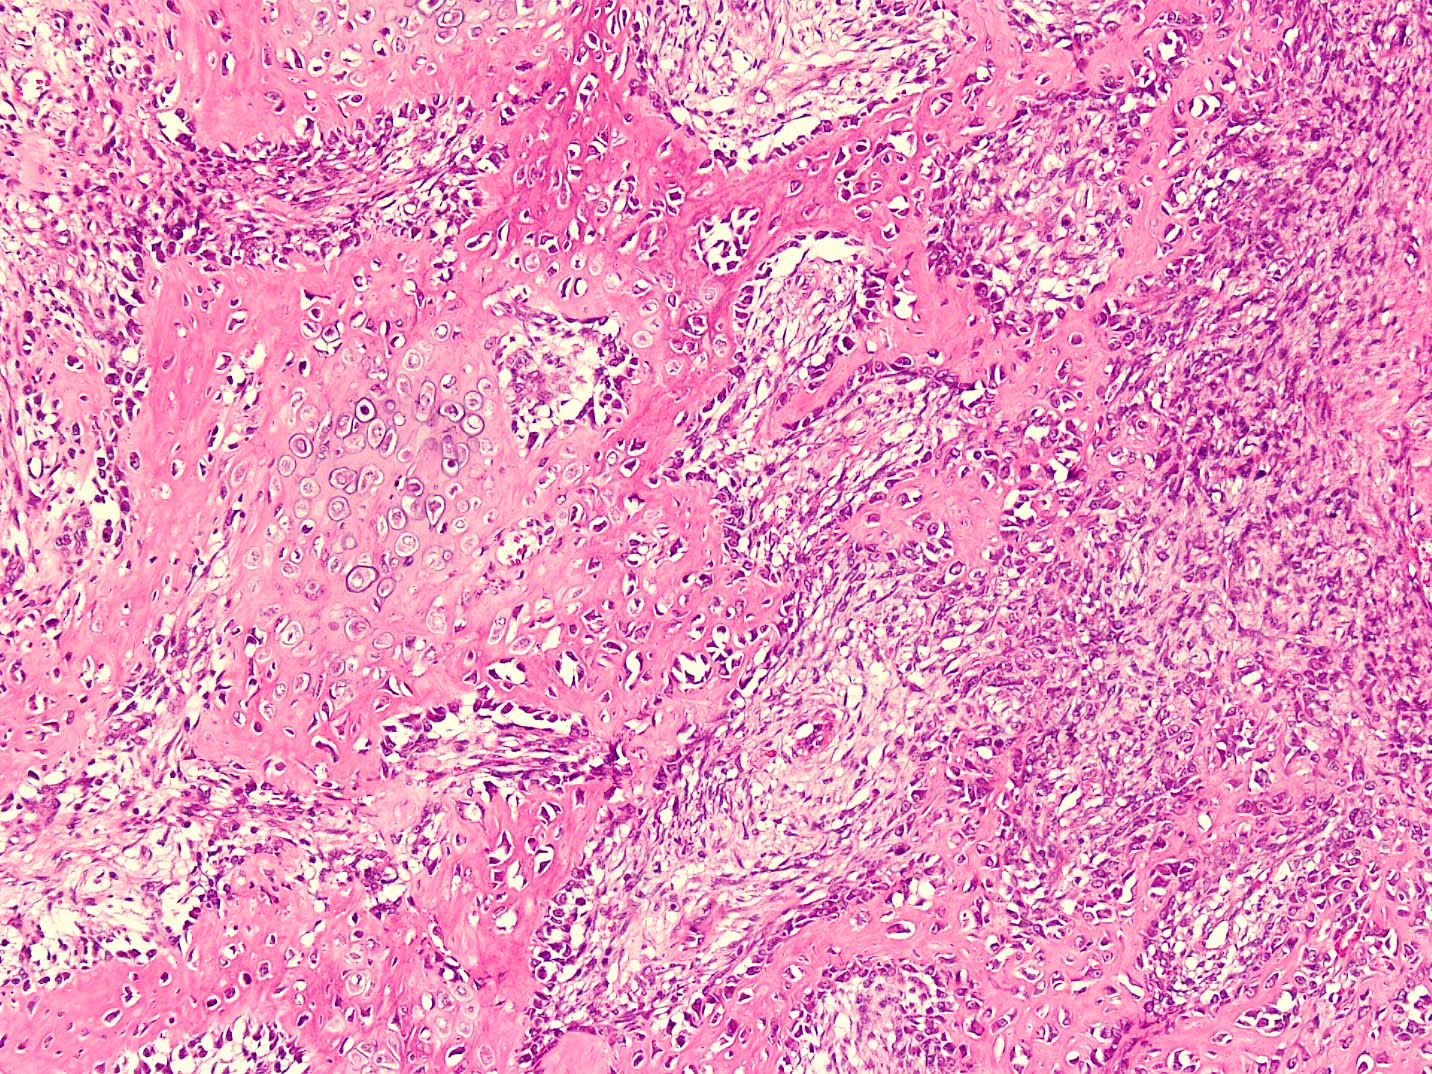

- Histologically, zonal pattern is characteristic with different degrees of cellular differentiation (inner zone, intermediate zone and peripheral zone)

- Intermediate zone:

- There is a mixture of fibroblasts and osteoblasts along with erratic osteoid separated by small sized vessels

- Scattered chondrocytes may be appreciated

- Peripheral zone:

- Osteoid undergoes calcification and leads to lamellar bone formation

- Islands of mature or immature cartilage may be present

- Extreme periphery / margin shows mature bone with osteoblastic rimming and little to no pleomorphism

Microscopic (histologic) images

- Comment: The sections from the mass show a circumscribed lesion with characteristic zonal pattern, with inner zone showing tissue culture-like background, against which are seen plump fibroblasts and myofibroblasts. This area is rimmed by immature bone in the middle and mature lamellar bone at the periphery.

B. Myositis ossificans. The given history in this case shows that the patient is physically active and provides short duration history of the lesion. The radiological findings suggest a lesion with maturation at periphery. The microscopic image shows characteristic zonation. These are all features of myositis ossificans.

B. Myositis ossificans. The question describes a detailed microscopic description of myositis ossificans. The lesion is not osteosarcoma because it is circumscribed and shows zonation in the form of mature periphery and immature center. This is contrary to osteosarcoma. Nodular fasciitis does not show heterotopic ossification and zonal pattern, although the center of myositis ossificans is reminiscent of nodular fasciitis.